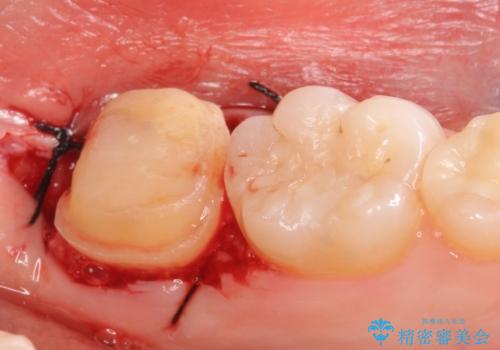

左下7遠心(下記のX線写真の左側)の歯質が歯肉縁下でかつポケットも深かったため、歯茎を下げる歯周外科を行いました。

その後歯茎の治りを待ちポケットが正常値であることを確認後、オールセラミッククラウンによる補綴を行いました。

- 外科手術のため、術後に痛みや腫れ、違和感を伴います